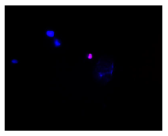

| Control | Doxycycline (DOX) | DOX + C1 | DOX + C2 | |

| SH-SY5Y cells | ||||

| Hoechst 33342 + propidium iodide | ![]() | ![]() | ![]() | ![]() |

![]() | ![]() | ![]() | ![]() | |

| HepG2 cells | ||||

| HEK-293 cells | ||||

2.3. The Morphological Changes and Death of Cells

4.1.8. Apoptosis and Necrosis Death Cells